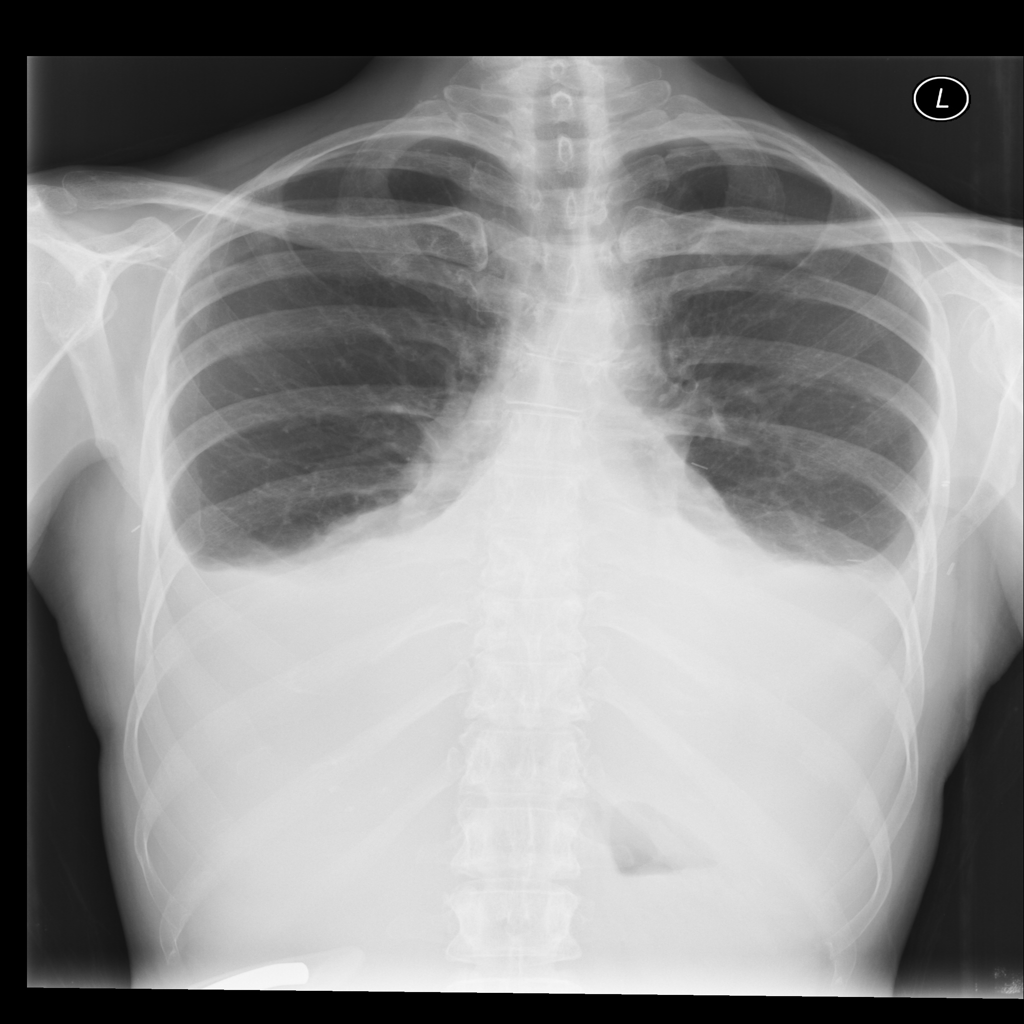

PAT-40F9 · IMG-004Effusion

PAT-40F9 · IMG-004

PA